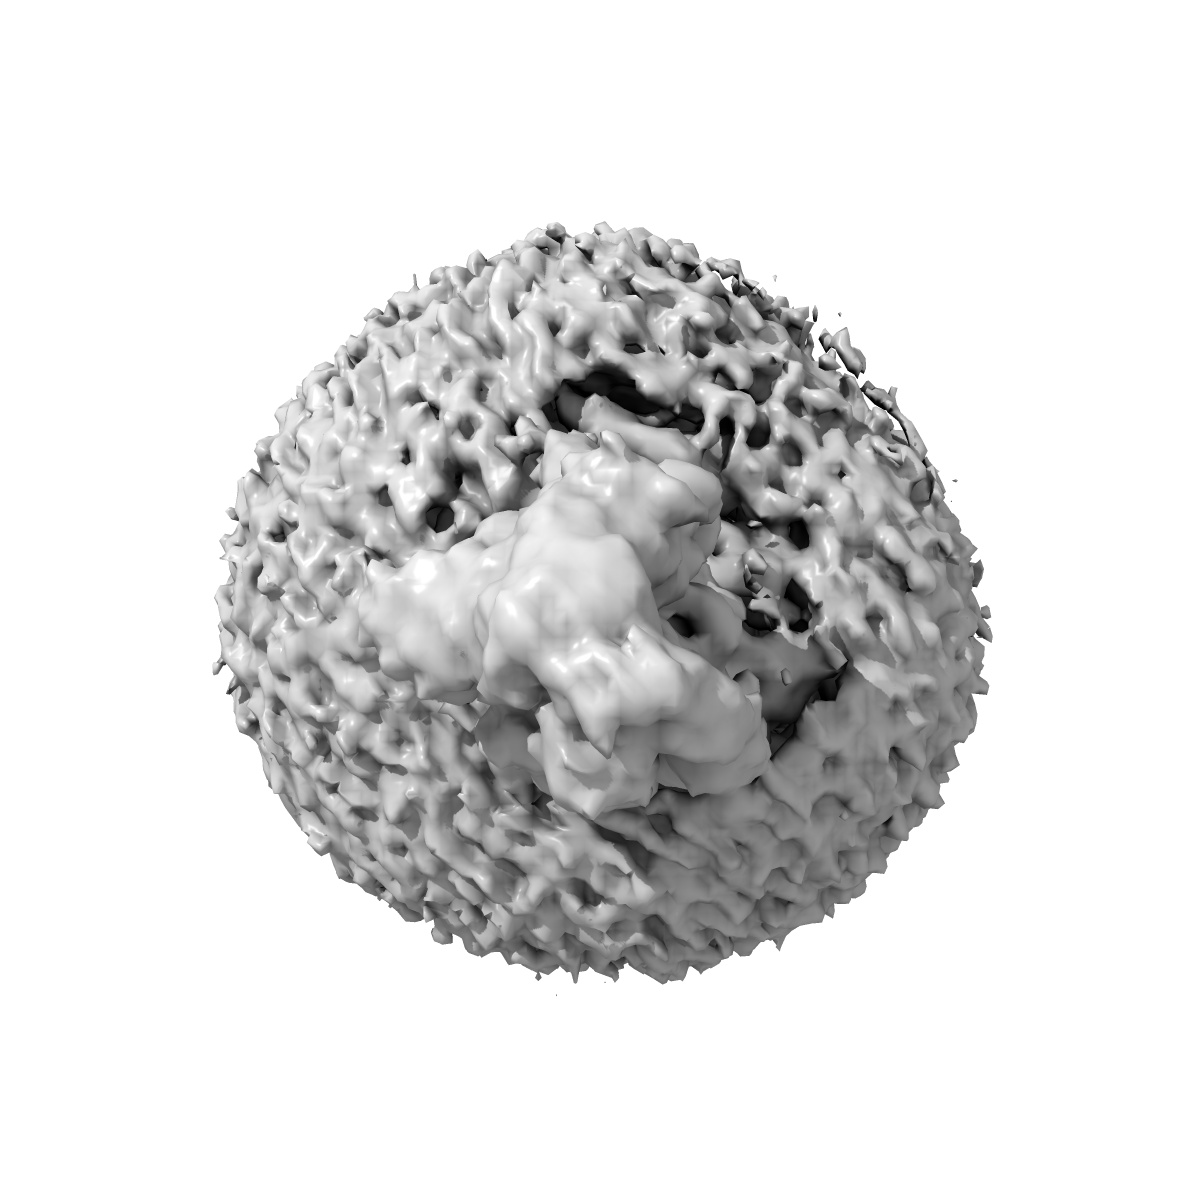

Cryo-EM structure of the retatrutide-bound human GLP-1R-Gs complex

Single-particle2.68 Å

Sample: Cryo-EM structure of the human glucagon-like peptide-1 receptor in complex with Retatrutide and G protein

Structural insights into the triple agonism at GLP-1R, GIPR and GCGR manifested by retatrutide.